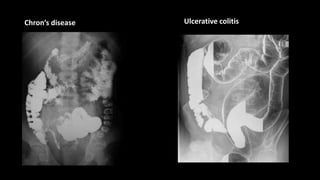

Chron’s disease Ulcerative colitis